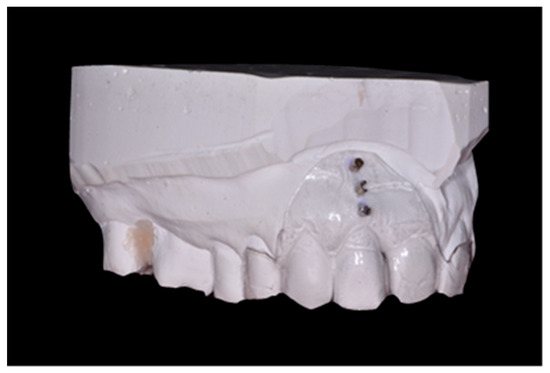

- Soft tissue thickness in the root projection of the extracted tooth (3 mm, 6 mm and 9 mm from gingival margin of extracted tooth); to measure this parameter, an individual positioner with holes for the measuring tool was prepared before tooth extraction (Figure 2); a sharply pointed root canal tool No. 25 was used for the test; in order to perform measurements in the same point, through the embedded sleeves, a root canal tool No. 25 was passed through and the puncture was performed to determine the measurement point; after removing the stent in the marked areas, the tissue was punctured until palpable bone resistance was felt; measurements were made under local anesthesia.

Figure 2. Individual positioner with holes for measuring tool.